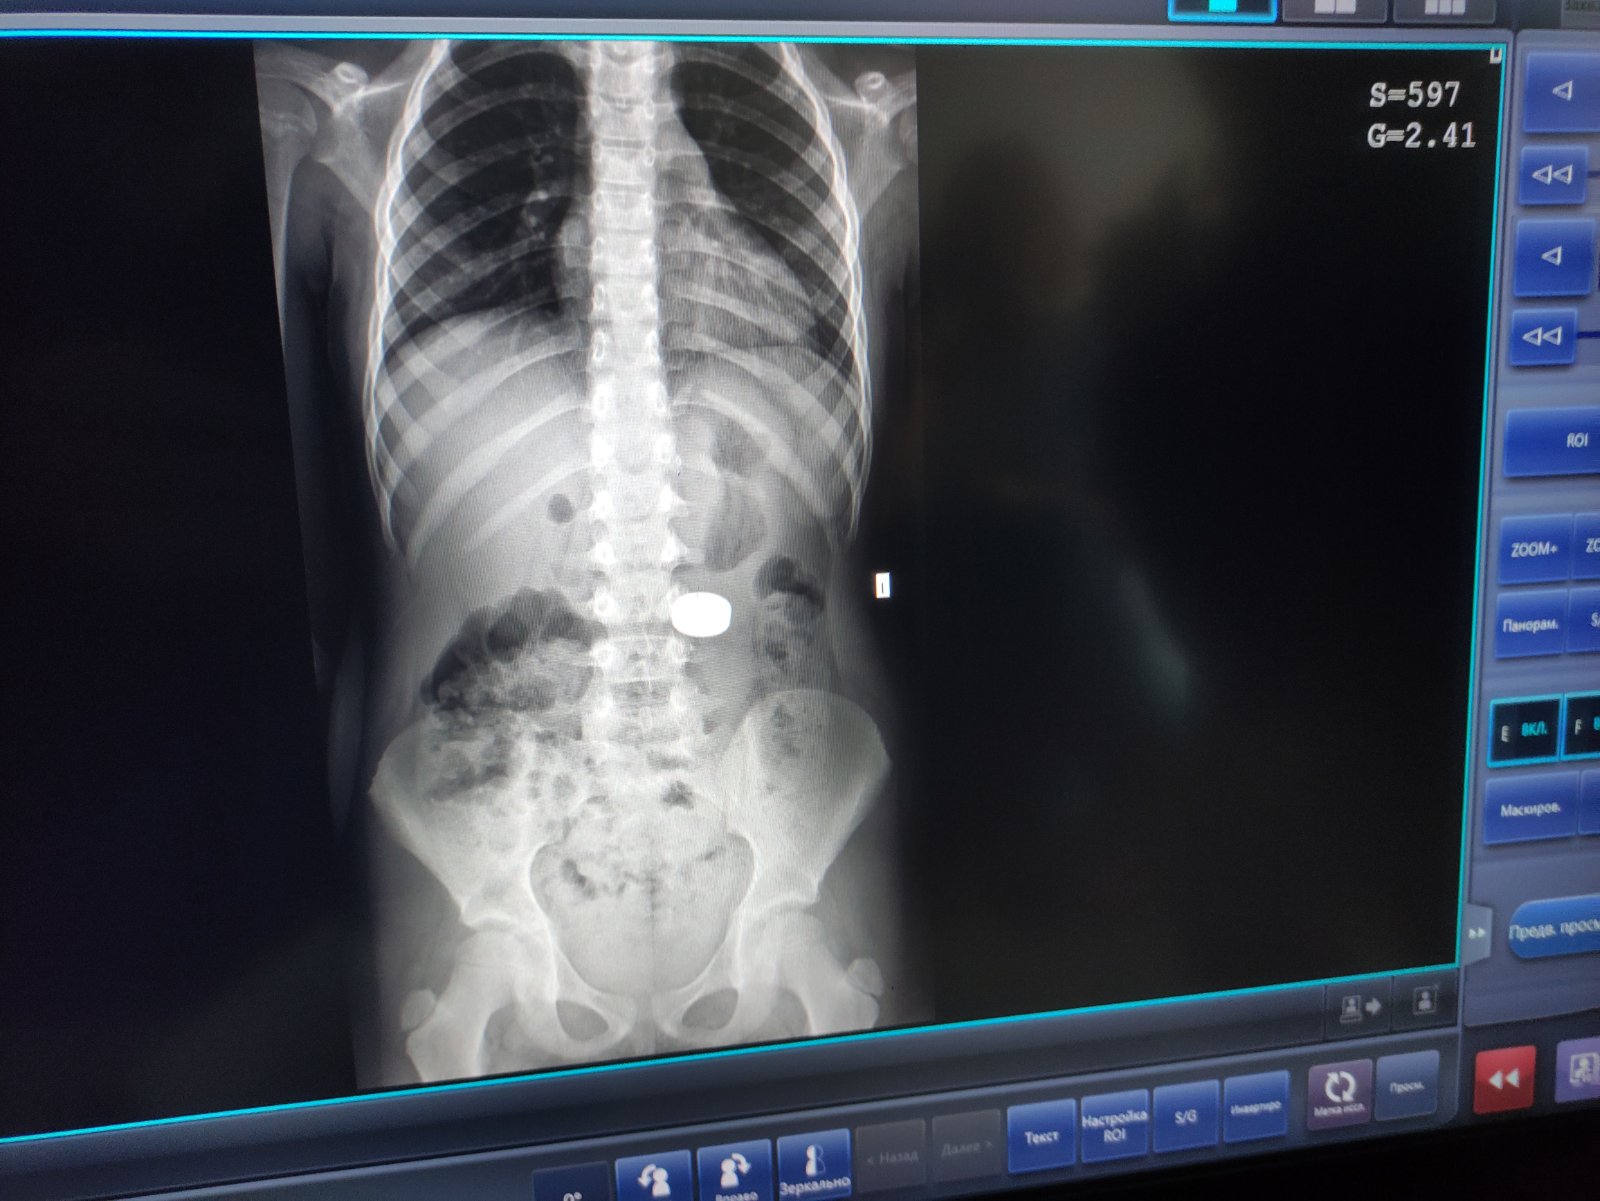

"Магніти були великого діаметра. Під їхньою вагою шлунок опустився до рівня тазових кісток. Тому спочатку візуально вони локалізувались у кишківнику. Проте ми провели пацієнтці додаткове рентгендослідження у лежачому положенні, і зрозуміли, що сторонні тіла ще у шлунку, тож можна видалити їх ендоскопічно", - додав фахівець.

У Львові зі шлунка дитини дістали магніти (фото: facebook.com/zusdmc)